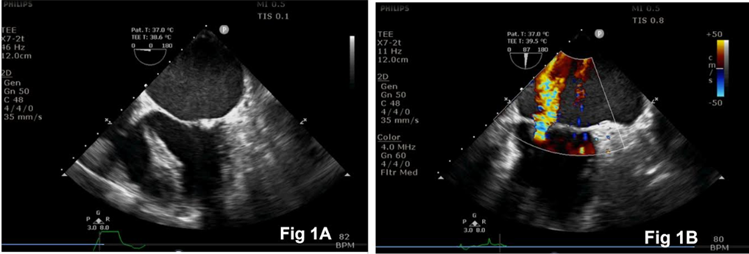

A 48-year-old man presented with worsening dyspnea and palpitations and was admitted for evaluation. Transthoracic echocardiography indicated severe mitral stenosis, moderate mitral regurgitation, and mild tricuspid regurgitation. The patient underwent mitral valve replacement surgery. After the induction of general anesthesia, a transesophageal echocardiography (TEE) probe was inserted, confirming the preoperative findings (Fig.1). The right internal jugular vein was cannulated for the insertion of an introducer sheath and PAC by a skilled anesthesiologist. The integrity of all ports and the inflation and deflation of the PAC balloon (Edwards Lifesciences LLC, CA, Irvine, USA) were confirmed before insertion (Fig. 2A, 2B).

Figure 1: Intraoperative transesophageal echocardiography images showing mitral stenosis (Fig. 1A) and mitral regurgitation (Fig. 1B).